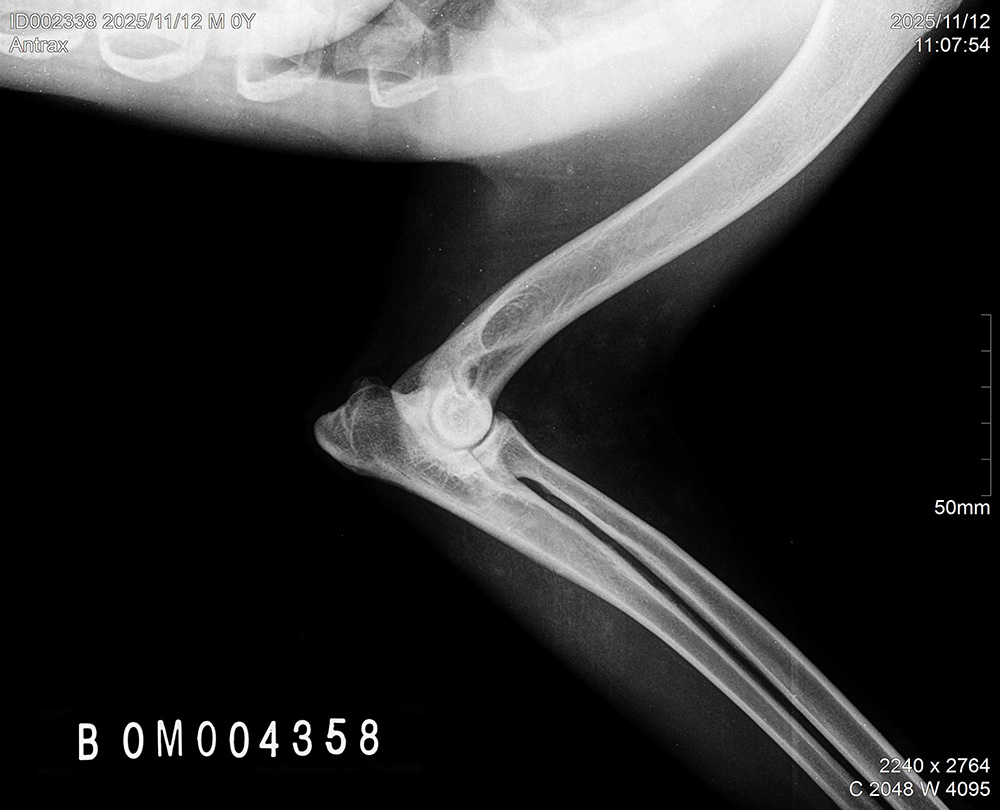

| ANTRAX, DOB July 2 2024, elbows/hips/spine: see x-rays below. ATRAX is almost 2 years old malinois male that was raised in the kennel. He is used to stay both inside the kennel as well as inside of house. He is good with other dogs and has no problem with other animals. ATRAX is a normal social dog and he gets used to the new handler and environment quickly. ANTRAX doesn't have problem with any kind of surface. ANTRAX has excellent ball drive. He is able to search for hidden ball in very hard environments and conditions. He searches with great interest and persistance until he finds the ball. His protection is also excellent. He has fast and hard bites. He is able to work inside and outside of buildings and he can bite on sleeve as well as bite suit. ANTRAX is suitable as a dog for personal protection or as a dual purpose law enforcement dog. |

X-RAYS: